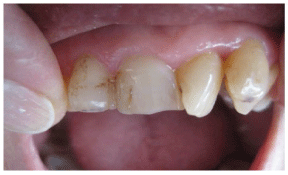

Dentistry today offers many modes of tooth correction in position, shape, alignment, and shades. Some of us offer orthodontia, implants, and full tooth reduction crowns. Materials vary but center around porcelain or porcelain modified materials made of silica or zirconia to metal.